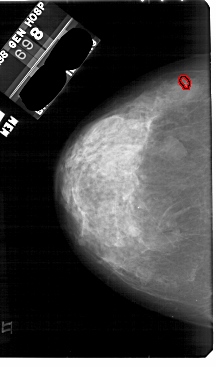

A_1844_1.LEFT_MLO

LEFT_MLO LINES 5491 PIXELS_PER_LINE 3406 BITS_PER_PIXEL 12 RESOLUTION 43.5 OVERLAY

FILE: A_1844_1.LEFT_MLO.OVERLAY

TOTAL_ABNORMALITIES 1

ABNORMALITY 1

LESION_TYPE CALCIFICATION TYPE PLEOMORPHIC DISTRIBUTION CLUSTERED

ASSESSMENT 4

SUBTLETY 3

PATHOLOGY BENIGN

TOTAL_OUTLINES 1

BOUNDARY